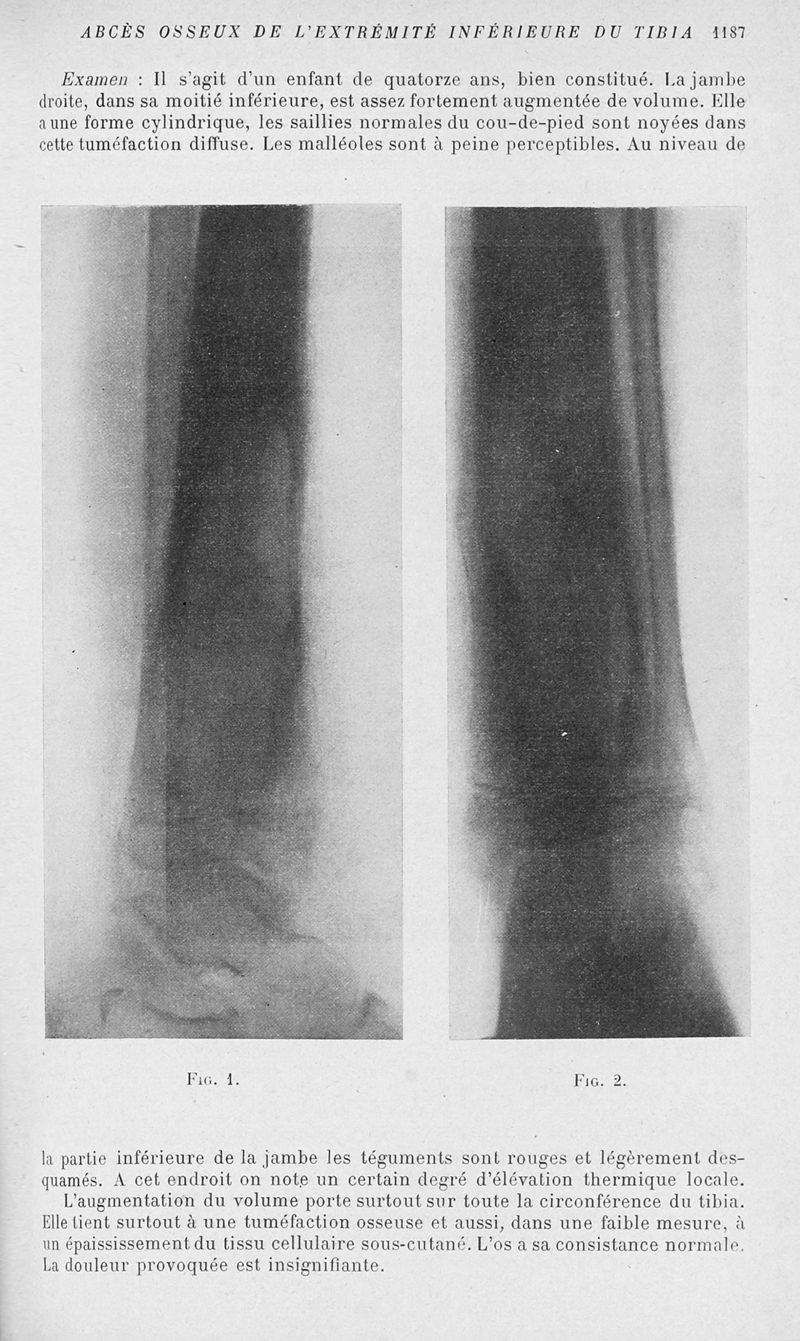

Bulletins et mémoires de la société nationale de chirurgie

Tome LIII, 1927. - Paris : Masson, 1927.